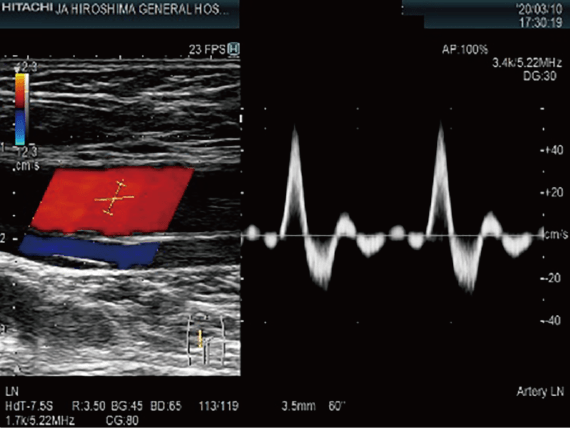

頸動脈超音波検査

胸頸部より超音波を照射し,頸動脈を観察する検査です。動脈硬化やプラークによる血管狭窄・閉塞などの評価に用いられます。

上肢・下肢血管超音波

上肢や下肢から超音波を照射し,動脈や静脈を観察する検査です。静脈では,エコノミークラス症候群に代表される静脈内血栓や静脈瘤の評価に用いられます。動脈では,動脈硬化の程度や血管狭窄・閉塞などの評価に用いられます。